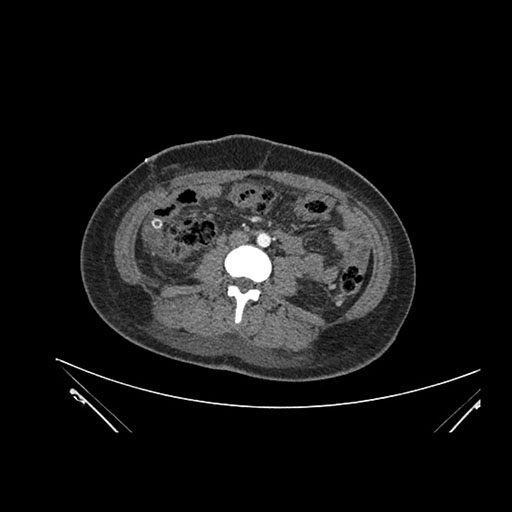

Axial Arterial

Axial Venous

Coronal Arterial

Coronal Venous

Imaging analysis

Based on initial findings, which issue(s) would you be most concerned about?